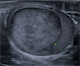

|Have a high index of suspicion for ectopic pregnancy

24 Mar 2020

Ectopic pregnancy is estimated to occur in 1-2% of all pregnancies and continues to be the leading cause of maternal mortality in early pregnancy. Most ectopic pregnancies are located within the fallopian tube and carry a risk of tubal rupture and intra-abdominal bleeding. Women with ectopic pregnancy can present in a wide variety of ways, from acute collapse following rupture to asymptomatic and unaware that they are pregnant. Symptoms may include vaginal bleeding and abdominal pain. There may also be non-specific symptoms such as Gl and urinary symptoms, rectal pressure, dizziness, shoulder tip pain, fainting or syncope.